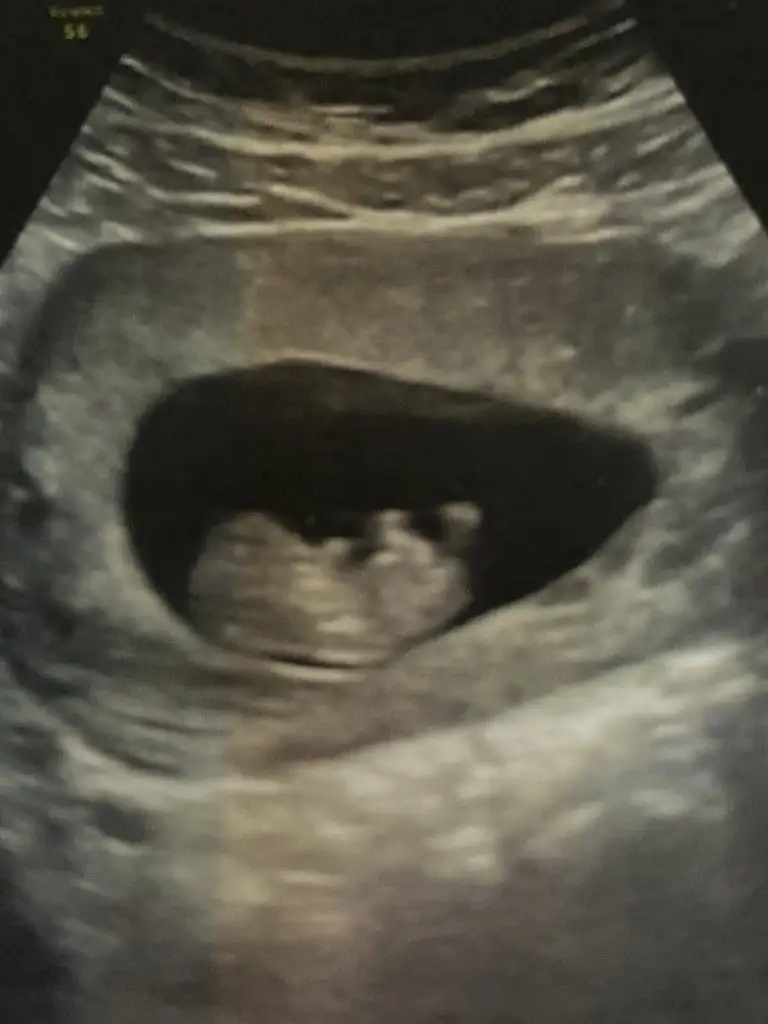

Nubu görünmüyorCanim benimkine de bakarmisin

Merhaba bende meraktan buralardayımvakit ayırabilirseniz birde bizim tahminde bulunabilirmisiniz

Buna da bakabilir misiniz yarın yeni kontrolüm var bakalım doktor nediyecekNubu görünmüyor